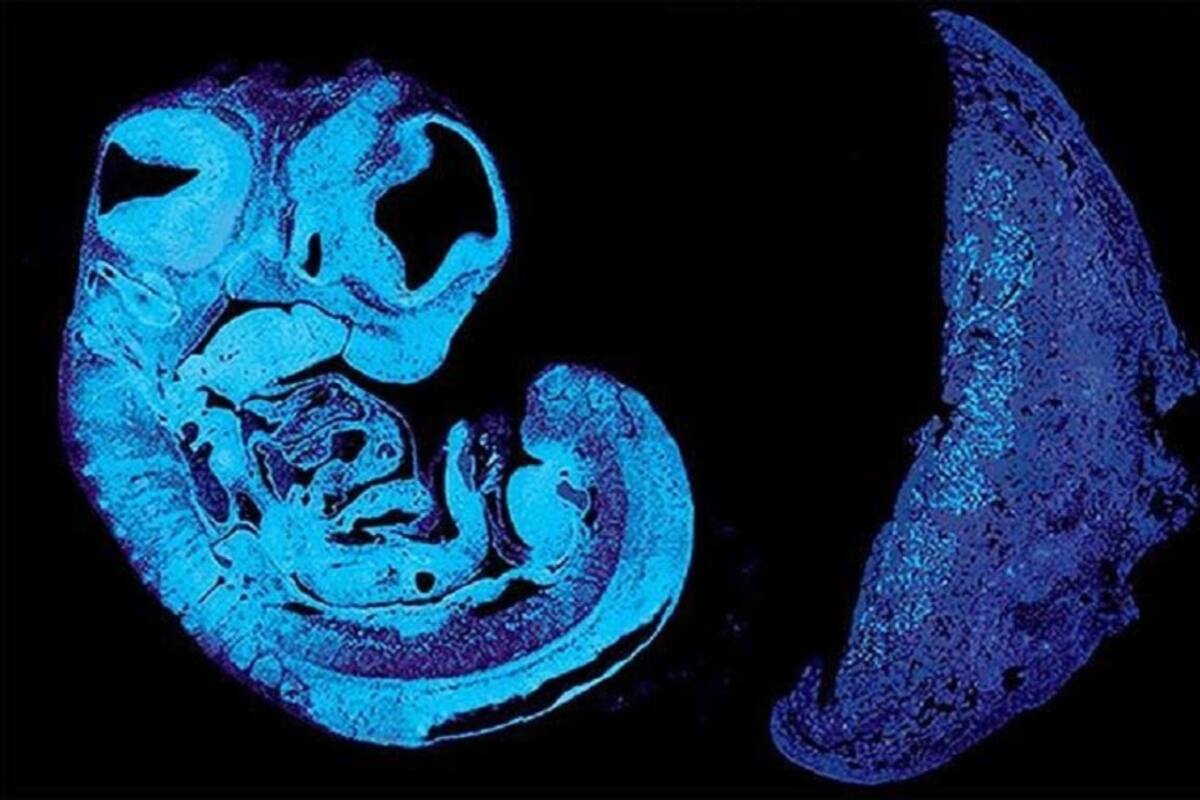

Utilizando ratones modificados genéticamente los expertos identificaron una señal clave que el feto produce para estimular el crecimiento de los vasos sanguíneos dentro de la placenta que, en conjunto con otras modificaciones celulares, permiten una mayor entrada de sustancias alimenticias, señala la investigación.

Esa señal, conocida como IGF2, llega a la placenta a través del cordón umbilical. Altos niveles de esta proteína se asocian con un mayor crecimiento del feto. Esta se expresa gracias a la activación de un gen heredado del padre, pero no es la única proteína que regula la correcta expansión de los vasos sanguíneos, indica RT. Según lo visto en los ratones, existe otra llamada IGF2R, que se expresa gracias a la activación de un gen heredado de la madre.

La fisiología y biología de los ratones muestran muchas similitudes con las de los humanos y han permitido a los investigadores modelar el embarazo humano. Este último hallazgo contribuye a la comprensión de cómo el feto, la placenta y la madre se comunican entre sí durante la gestación.